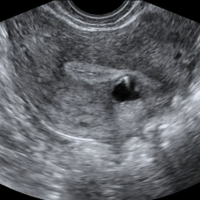

子宫内膜异位症和子宫腺肌症发病部位、原因、病理、治疗方法、临床表现都是不同的。子宫内膜异位症,简称内异症,是指具有生长功能的子宫内膜组织出现在子宫腔被覆黏膜以外的身体其他部位所引起的一种疾病。子宫腺肌症在医学术语上称为子宫腺肌病,这是子宫内膜异位性疾病的一种。两者还是有很明显的区别,大家在诊断的时候一定要去正规医院,然后对症治疗。子宫内膜异位症和子宫腺肌症的区别很多女性对于子宫腺肌症和子宫内膜异位